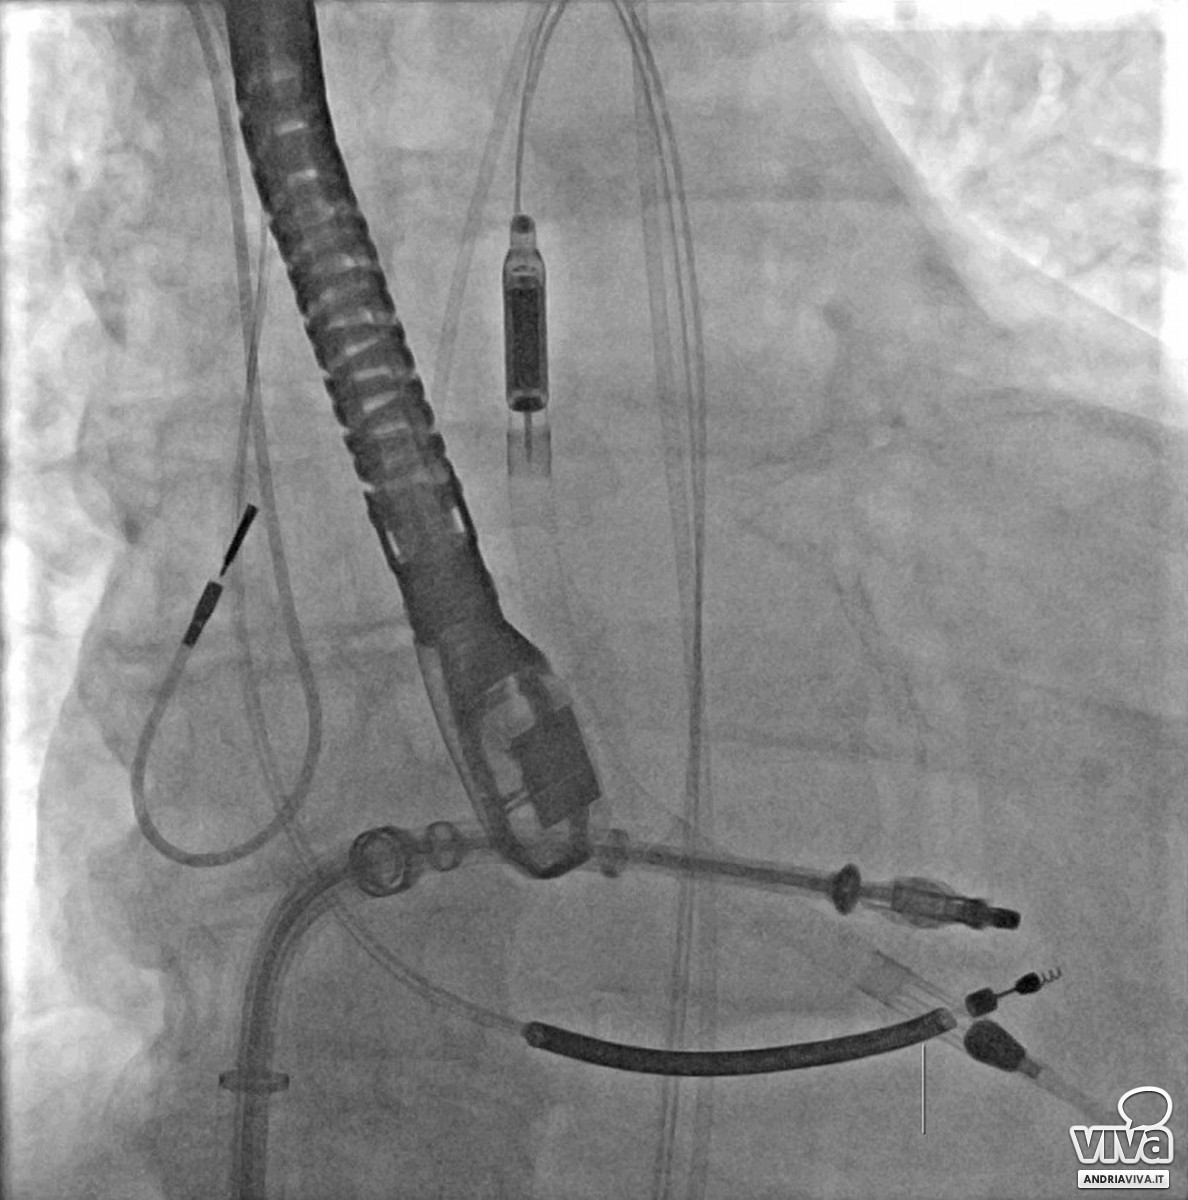

È accaduto presso il Bonomo di Andria, per la prima volta in Puglia, è stato eseguito su un paziente 62enne un complesso intervento combinato di riparazione trans catetere di mitrale con il supporto del sistema di assistenza ventricolare Impella, che funge da pompa microassiale intravascolare per supportare temporaneamente la funzione cardiaca, del ventricolo sinistro, in caso di grave sofferenza o shock cardiogeno.

"A causa della severa disfunzione della contrattilità cardiaca - spiega il dott. Claudio Larosa, cardiologo emodinamista che ha eseguito l'intervento - anche l'intervento trans catetere avrebbe comportato notevoli rischi procedurali. Si è, pertanto, pianificata la riparazione della valvola mitralica trans catetere con utilizzo contemporaneo di un sistema di assistenza ventricolare sinistra. Tale dispositivo, chiamato Impella, è stato posizionato all'interno del cuore attraverso un accesso arterioso di grosso calibro ad ha avuto l'obiettivo di supportare la funzione del cuore, severamente compromesso durante l'intera durata della procedura interventistica, evitando che il paziente potesse scompensarsi. L'intervento è stato portato a termine con successo ed il paziente è stato estubato e risvegliato già a fine procedura ed è stato trasferito, in buone condizioni, in terapia intensiva cardiologica dove è stato prontamente assistito dal personale di reparto".

"Questo complesso intervento combinato di riparazione trans catetere di mitrale con il supporto del sistema di assistenza ventricolare Impella, mai eseguito prima in Puglia - prosegue il dott. Francesco Bartolomucci - ha consentito di intervenire in sicurezza e con pieno successo in un contesto clinico molto complesso. L'insufficienza della valvola mitralica è una patologia cardiaca con un'alta prevalenza. Si stima, infatti, che circa il 10% della popolazione di età uguale o superiore a 75 anni ne sia affetto. L'incompleta chiusura dei lembi mitralici causa un flusso di sangue retrogrado che, se non trattato, può portare alla congestione del ciclo polmonare, allo scompenso cardiaco ed alla disfunzione della funzione cardiaca. Le forme severe, se non trattate, sono associate ad una seria compromissione della qualità di vita".